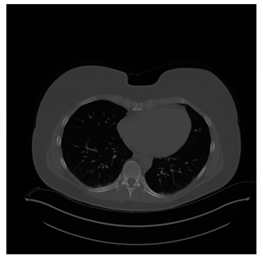

Figure 12.

Sampled images in the tested benchmark databases: (a) Breast-MRI-NACT-Pilot (breast), (b) ACRIN-DSC-MR-Brain (brain), (c) NIH (chest), (d) Lung-PET-CT-Dx (lung), (e) Prostate-MRI (prostate), and (f) Other grayscale standard images.

- Lung-PET-CT-Dx Database (available at: https://wiki.cancerimagingarchive.net/pages/viewpage.action?pageId=70224216 (accessed on 4 November 2021))

Lung-PET-CT-Dx is a CT-type image database collecting lung medical images. Some samples are shown in Figure 12d.